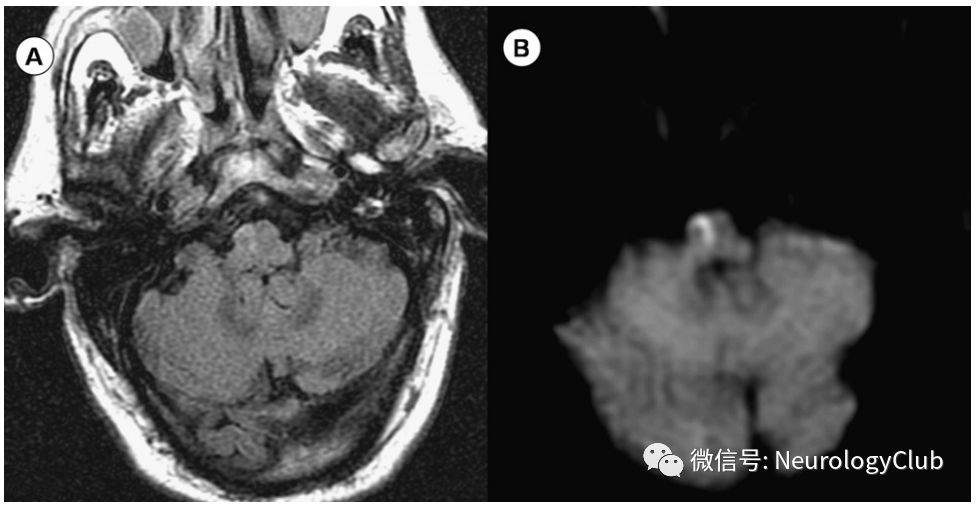

经典的三联征包括病灶对侧偏瘫,对侧位置觉振动觉的缺失以及同侧舌肌无力,并不总是出现(图2)。也可有眼球活动异常和构音障碍。

图2:Dejerine综合征;58岁患者,突发眩晕、左侧偏瘫、左侧偏身感觉障碍和共济失调;A:T2WI可见右侧延髓内侧高信号病灶;B:DWI提示弥散受限

患者可表现为同侧声音嘶哑和软腭瘫痪,同侧面部感觉缺失,同侧Horner综合征(眼睑下垂,瞳孔缩小,无汗),同侧共济失调以及同侧面部和对侧躯干痛温觉缺失(图3)。此外还可:有眼球震颤,眩晕,恶心和复视。常因椎动脉(75%)、小脑后下动脉(10%)以及基底动脉血栓形成所致。

图3:Wallenberg综合征;46岁女性患者,表现为交叉性感觉障碍、Horner综合征、眩晕、复视、共济失调、恶心和吞咽困难;A:T2WI可见右侧延髓外侧高信号病灶;B-C:DWI和ADC证实为急性梗死;D:MRA提示右侧椎动脉夹层